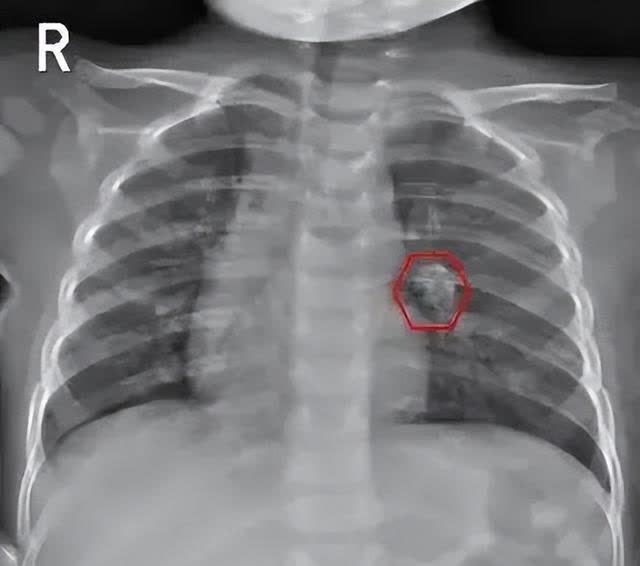

肺结核的影像学表现及鉴别诊断

肺结核的影像学表现及鉴别诊断

肺结核的影像学表现及鉴别诊断

肺结核的影像学表现及鉴别诊断

肺结核的影像学表现及鉴别诊断

肺结核的分型及影像学表现

肺结核的影像学表现及鉴别诊断